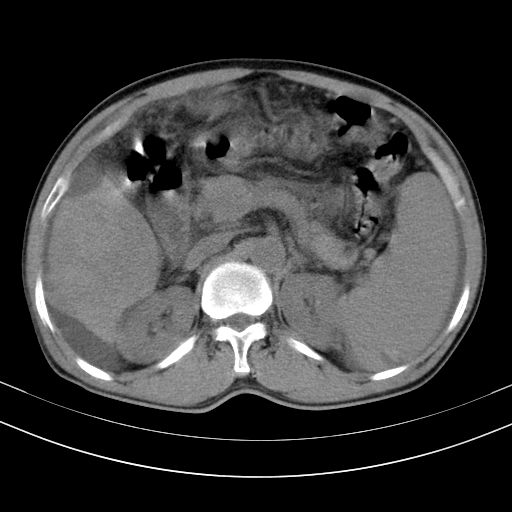

以下是引用随光逐影在2010-2-28 10:23:00的发言:[br]1)考虑肝癌;建议行ct增强扫描检查。2)肝硬化,脾大,腹水。3)慢性胆囊炎。

以下是引用dyqct在2010-2-28 16:44:00的发言:[br][quote]以下是引用随光逐影在2010-2-28 10:23:00的发言:[br]1)考虑肝癌;建议行ct增强扫描检查。2)肝硬化,脾大,腹水。3)慢性胆囊炎。